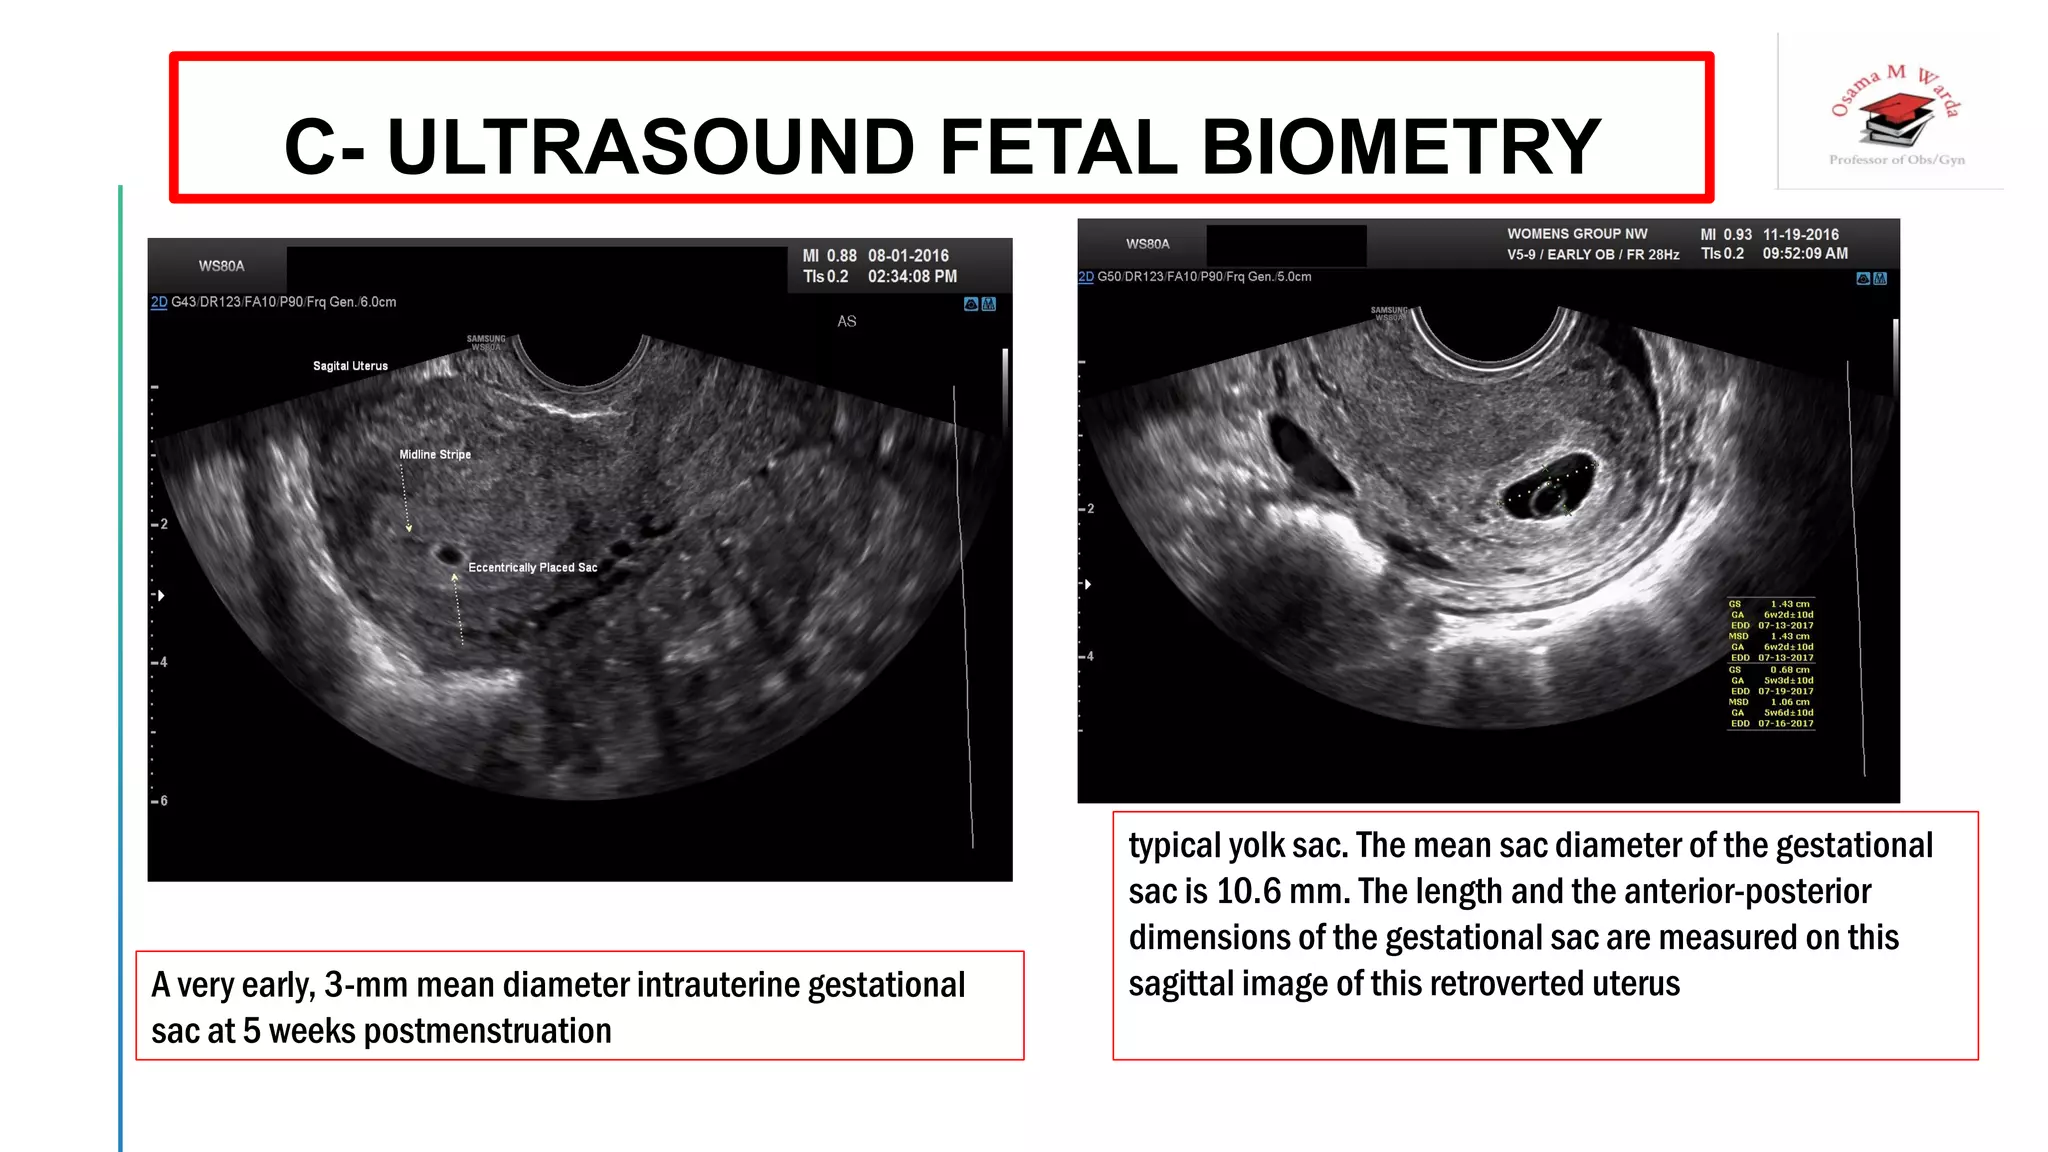

Gestational sac diameter (GSD)

 With a TVS, a 2- to 3-mm gestational sac can usually

be seen by 5 weeks from the last menstrual period .

 A yolk sac is usually seen by 6 menstrual weeks, or by

the time the mean diameter of the sac has reached 10

mm

 A fetal pole with heart tones is typically seen by the

completion of 7 menstrual weeks

A very early, 3-mm mean diameter intrauterine gestational

sac at 5 weeks postmenstruation

typical yolk sac. The mean sac diameter of the gestational

sac is 10.6 mm. The length and the anterior-posterior

dimensions of the gestational sac are measured on this

sagittal image of this retroverted uterus